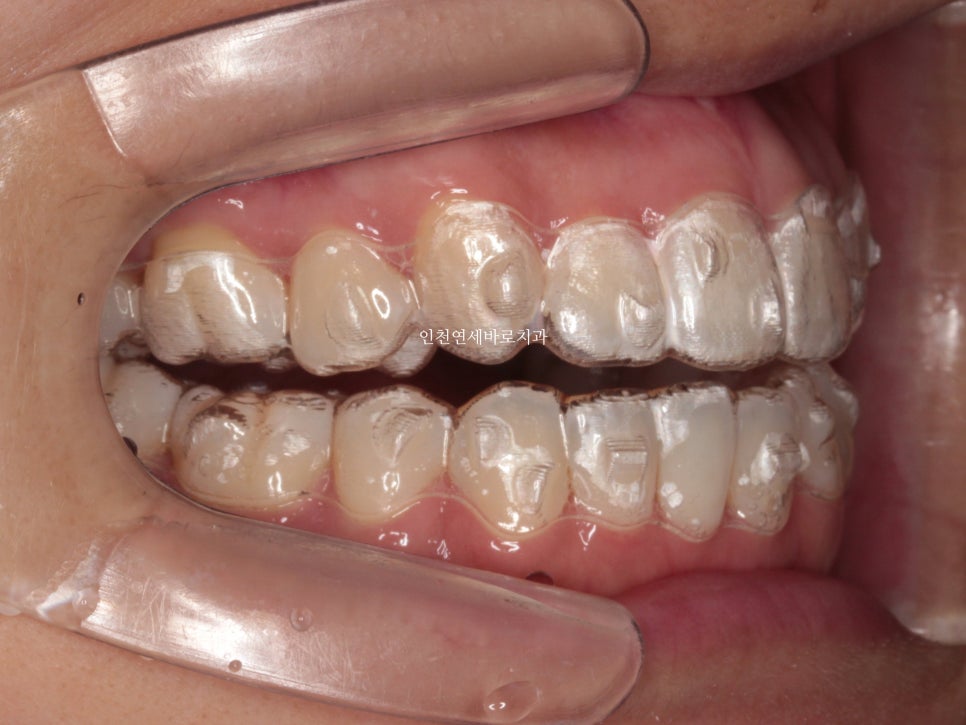

원하시는 대로 클리피씨를 붙이기로 했고 ㅠ

일반 장치로 진행을 이어갔습니다. 저로서는 너무 아쉬움

그래도 일단 목표한대로 끝내야하니 계속 치료를 이어갑니다

아마도 조금만 더 참고 꼈다면 인비절라인으로 잘 마무리 할 수 있지 않았을까 ㅠ